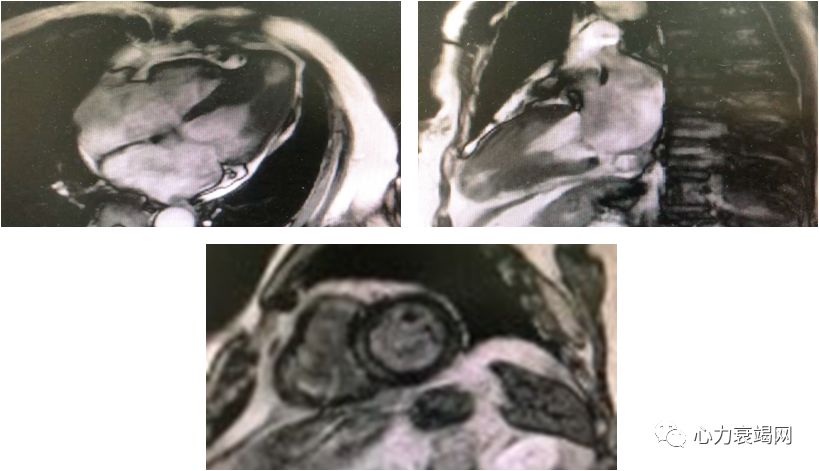

左房内径轻度增大,左室腔正常高限

左室室间隔中远段及侧壁中段室壁增厚,致左室中部梗阻(最厚约19~20mm)

心尖部室壁变薄,可见矛盾运动

延迟增强后心尖部可见明显透壁样强化

印象:肥厚性心肌病,左室心尖部室壁瘤形成

➤ 肥厚性梗阻型心肌病(左心室中部梗阻)

左心室中部收缩期梗阻或闭塞呈“沙漏形”或“哑铃形